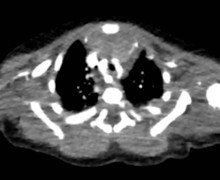

Un caso anomalo di stridor alla nascita: raccomandazioni per diagnosi e prevenzione delle complicanze del neonato con doppio arco aortico

Valencic I, Tarì EM, Moccia E, Vitali F, Corvaglia L.